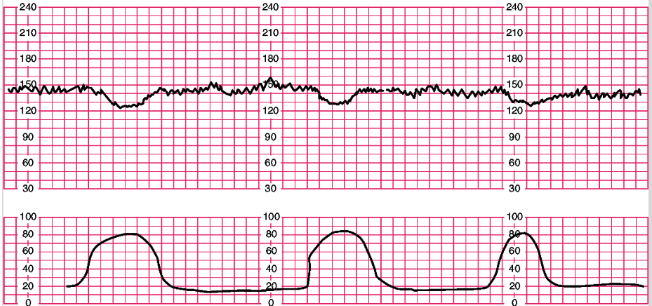

What is this? Explain why these occur. What are the nursing interventions?

An early deceleration

The head is compressed by uterine contractions.

Nursing interventions are to reposition the mother, continuous EFM, and support labor

Variable decelerations

This occurs because the cord is compressed.

Nursing interventions are to reposition the mother, amnioinfusion to flush fluids up to help float cord, give IVF, turn oxytocin off, and notify provider.

Late decelerations

They occurs because there is placental insufficiency.

Nursing interventions are to turn oxytocin off, position change, IVFs, sterile vaginal exam, notify provider, consider oxygen, and prepare women for potential C/S delivery.